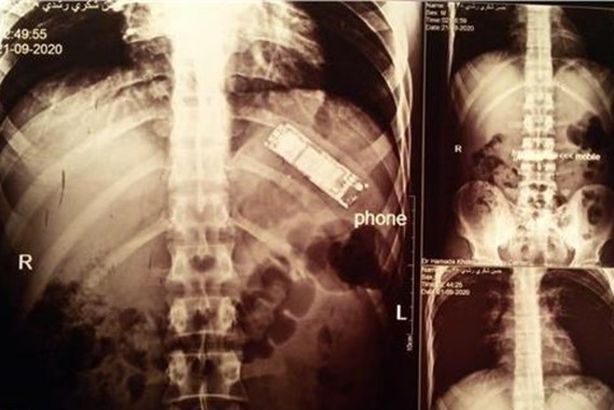

روى الطبيب محمد صلاح، تفاصيل استخراج هاتف محمول من بطن سجين مريض بمستشفى أسوان الجامعي.

وقال الطبيب، إن المريض المصاب سجين، وكان يشكو من ألم بسيط في بطنه، مشيرا:تم إجراء الأشعة له، وبعد المداولة معه اتضح أنه قام بابتلاع هاتف منذ 6 أشهر، وكان يريد تهريبه داخل السجن لاستعماله وعلق في بطنه ونسي الأمر.

وذكر أن “الهاتف المحمول صغير الحجم بحجم الصباع، وقام بلفه بكيس بلاستيك صغير لسهولة بلعه، ولمنع تأثير العصارة المعوية بالهاتف”.

ولفت إلى أن “المريض معتاد على فعل ذلك، ولكنه لم يستطيع إنزاله هذه المرة”، مبينا أن “الهاتف خرج سليم والمريض سليم وحالته جيدة”.